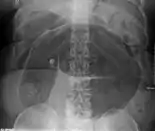

Coffee bean sign in a person with sigmoid volvulus

An x-ray of a person with a small bowel volvulus.